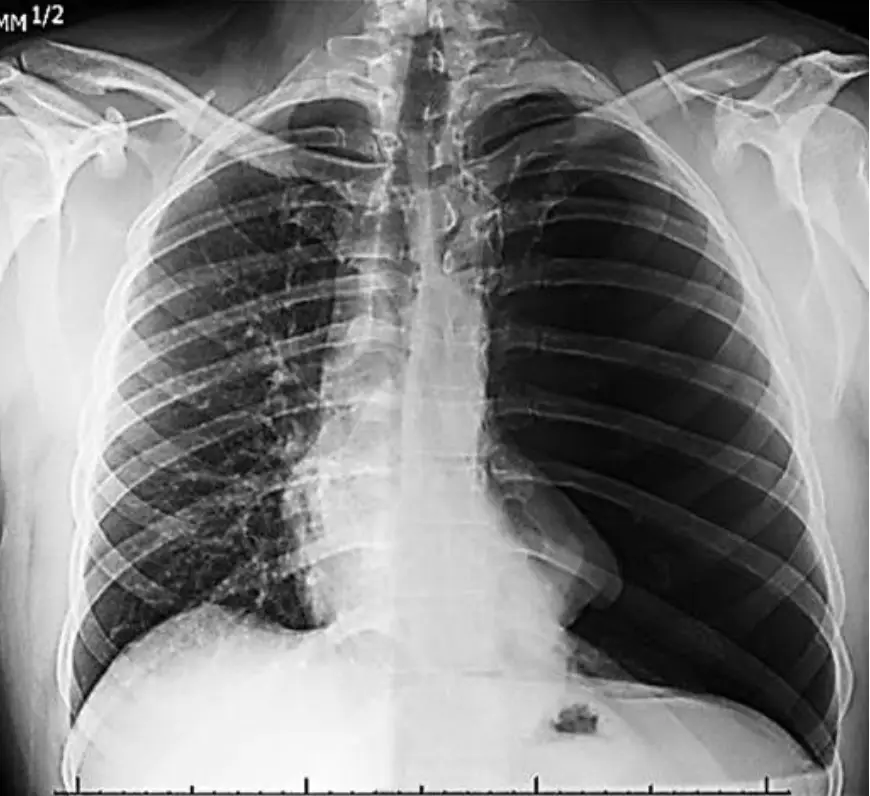

下圖胸部X光片,其最可能的診斷為何?

本題考的觀念是:如何由胸部 X 光辨識典型 pneumothorax(氣胸)的影像徵象與鑑別診斷。

• 片中左側胸腔可見一條明顯「白色內折的臟層胸膜線」,線外(胸壁側)完全沒有肺紋理,呈現均一透亮的空氣密度。

• 左肺實質被壓縮向肺門呈部分塌陷,與正常右肺對照,體積明顯縮小。

• 無肺門腫塊、支氣管樹擴張或浸潤影;也未出現明顯橫膈抬高或流動性液平面。

以上是大型單純性 pneumothorax 的經典表現。 -

B. 氣胸 (Pneumothorax) ‒ 正確

• 關鍵影像:白色臟層胸膜線+線外無肺紋理=胸膜腔內有氣體。伴肺實質向肺門回縮,即符合氣胸診斷。